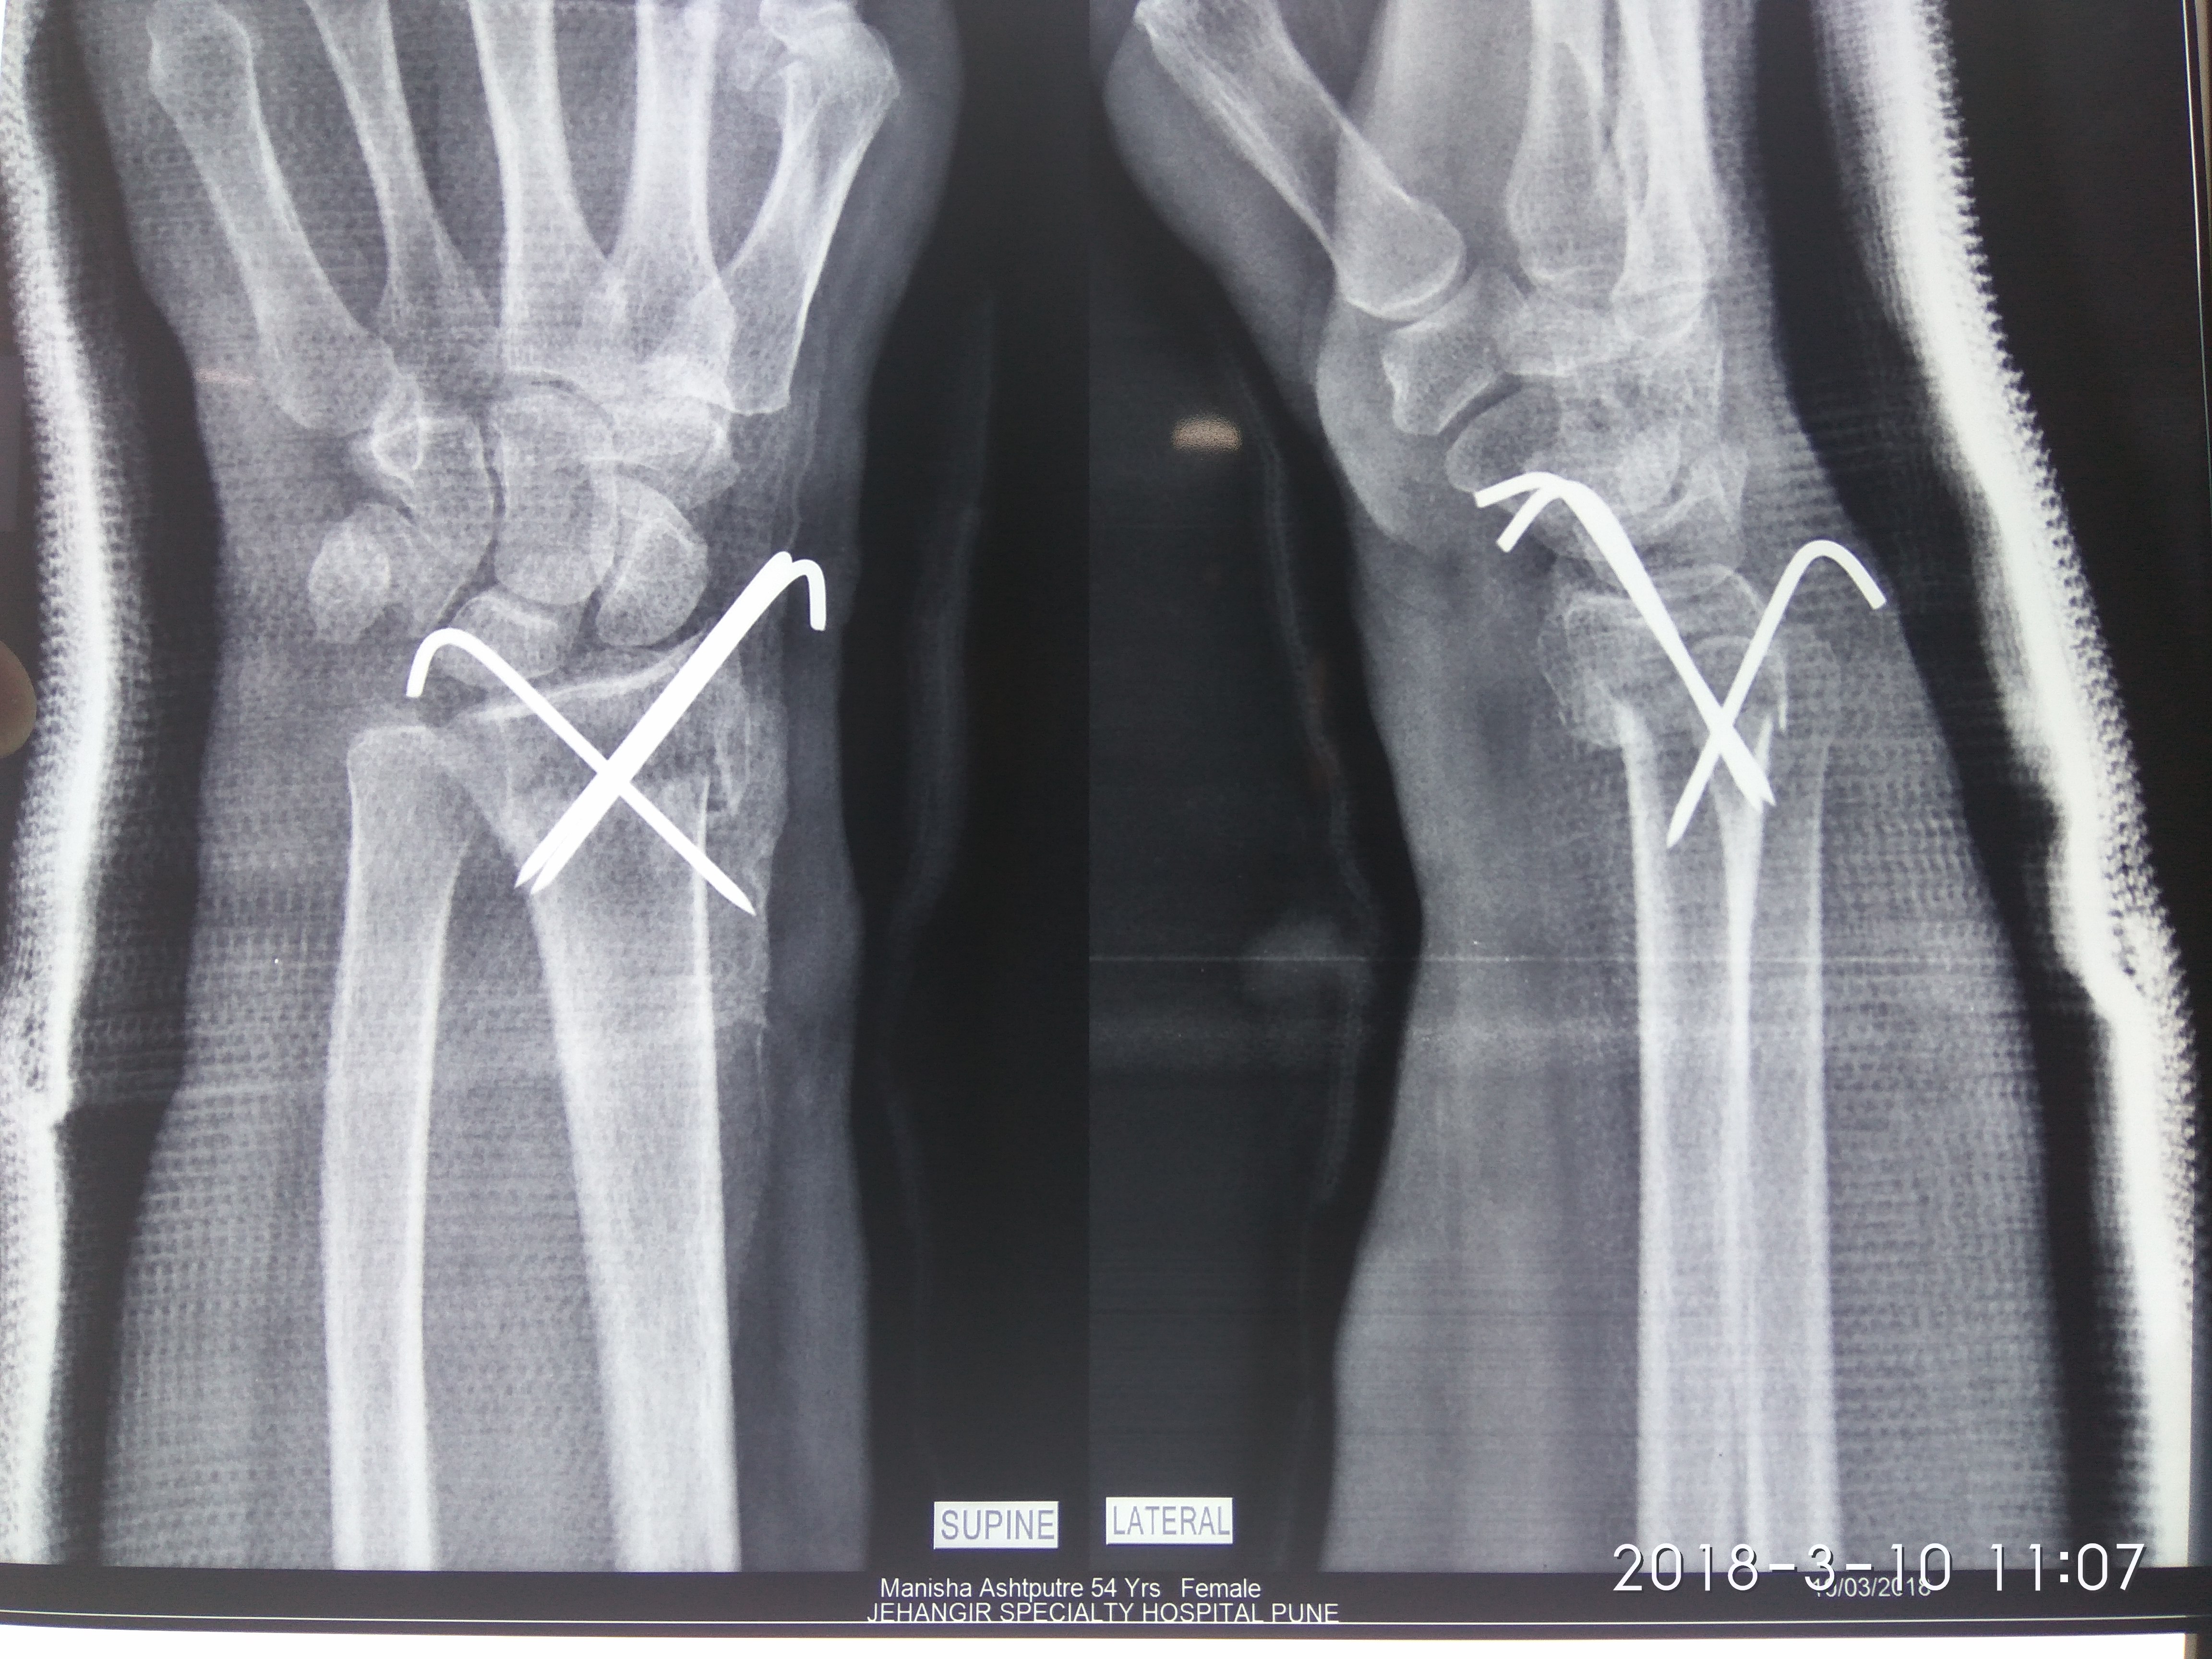

Dr. Sonawane Orthocare clinic is a centrally located Orthopedic Clinic In Pune city near Swargate at Hirabaug Business Centre, Hirabaug chowk, Tilak Road, Shukrawar peth and has easy accessibility from all parts of the city with multiple modes of travelling and enough parking spaces for patients’ own vehicles. Clinic is very modern and stylish and has air conditioned waiting area with comfortable sitting arrangement along with other amenities like TV, Wi-Fi, newspapers. There is hassle-free appointment and consultation system which is totally computerized. Patients get system generated appointment messages, reminders for follow-up dates and prescriptions through messages and emails. So its easy to keep track, keep and carry records and access it anywhere in the world. Clinic offers in-house digital X-ray, pathology tests and physiotherapy facilities at very reasonable rates. This makes the clinic a one stop destination for the patients they don’t need to go anywhere else for these facilities, saving lots of time and effort to get the treatment. We at Dr. Sonawane Orthocare clinic are committed for the best orthopedics care and proud to be one of the best orthopedics clinics in Pune.